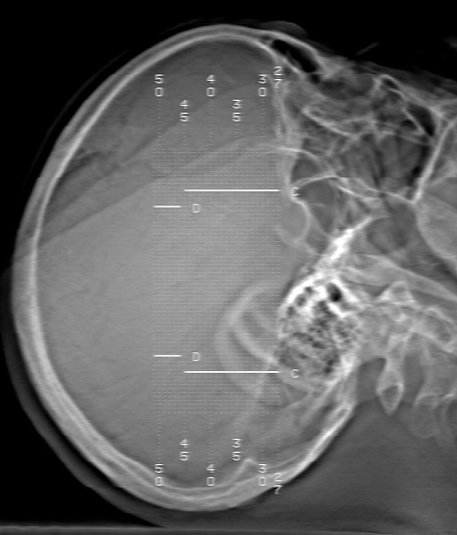

m70y, 2个月前发现左颞部有'包'隆起,近来自觉增大,无外伤无任何不适症状而就医,触诊包块质地较硬无移动无波动无皮温升高,胸片示右上肺陈旧结核....,ct扫描见左颞骨翼板局部内外骨板骨质破坏,似筛孔状,外板侧有骨膜线状增生,伴局部软组织丘状肿块,内板下梭形肿胀硬膜增厚翘起......颅内脑无异常.考虑骨良性病变 1.低度骨感染.   2.嗜酸性肉芽肿. 3.不排外骨结核...建议其穿刺活检,但患者失踪,追踪到结果定将公告.请大家分析.

左颞骨内板不光滑,密度减低,内板下可见新月形的软织密度影。脑实质轻度受压,外板外见膨胀形稍高密度影。考虑嗜酸性肉芽肿。建议增强扫描